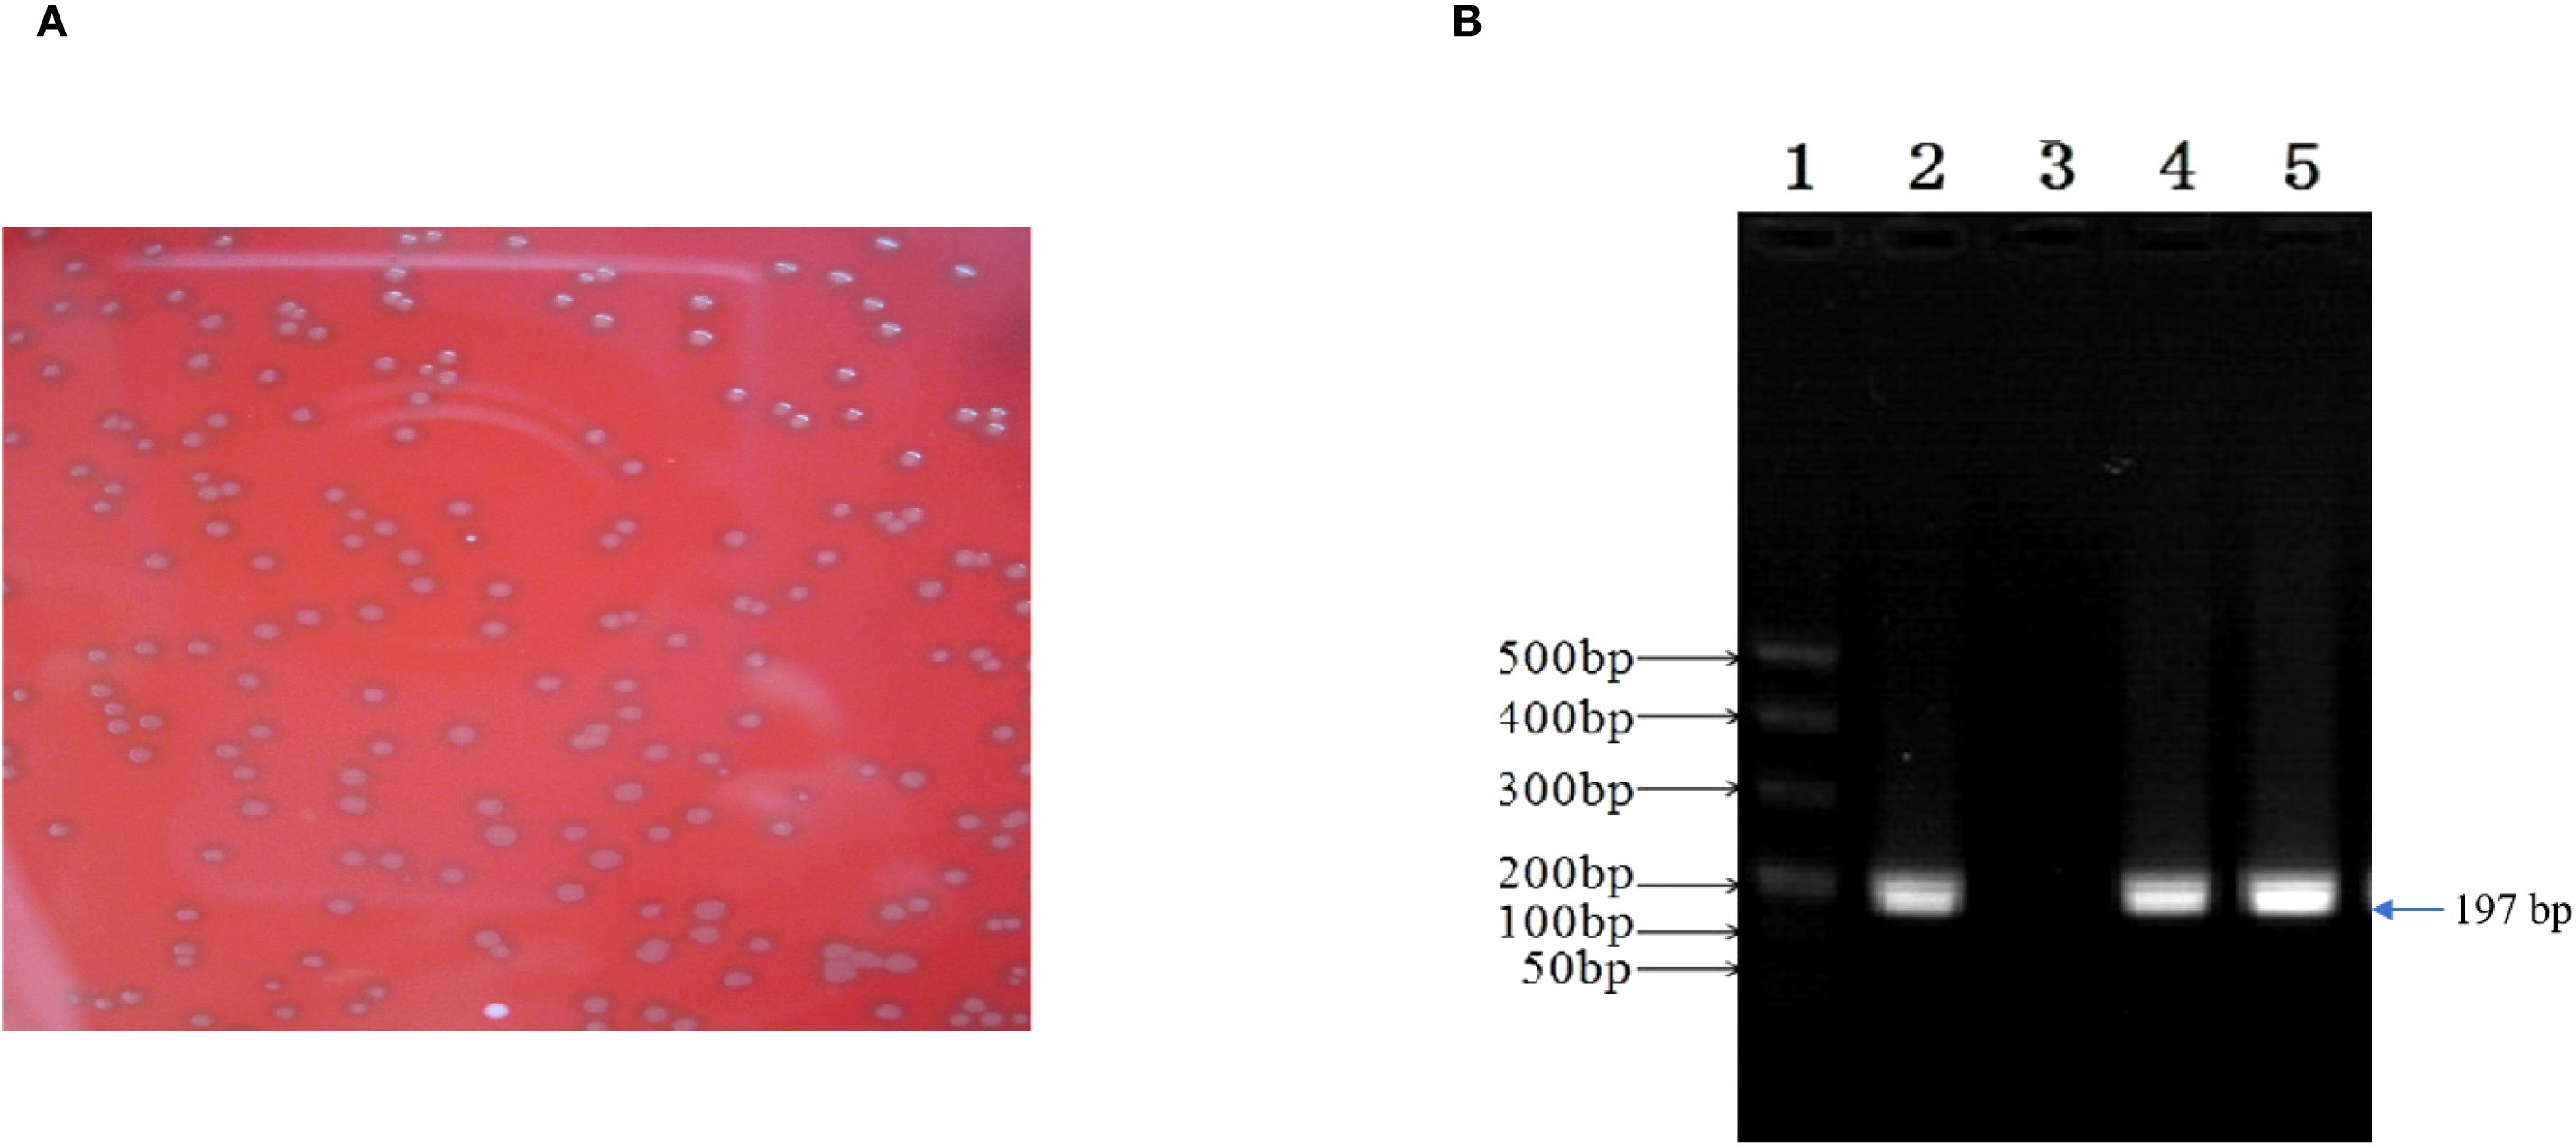

3.2 Isolation and characterization of E. faecalis

E. faecalis was successfully isolated in the alveolar lavage and throat swab using single-colony purification. Subsequently, the isolate was classified using biochemical assays and conventional PCR, and E. faecalis isolates were found to be Gram-positive, chain-forming, coccus-shaped organisms upon microscopic inspection (Figure 5A). The isolated strains were determined as E. faecalis using PCR. The DNA extracted from the typical colony produced the expected 197-bp PCR product of the target gene (Figure 5B); the sequence of the tuf gene was submitted to GenBank (accession number: SUB15618628), and NCBI blast was used. A sequence analysis of the tuf segment showed that the sequence from this isolate was 98%–100% homologous to the E. faecalis reference strains (GenBank # EU156939 and AY266992).

Figure 5. Enterococcus faecalis was isolated and identified from patient’s alveolar lavage and throat swabs. (A) Typical colonies of E. faecalis grew on Columbia Blood Agar Base Medium. (B) The isolate generated 197-bp PCR product. 1, marker; 2, positive control; 3, negative control; 4, patient’s alveolar lavage; 5, patient’s throat swab.